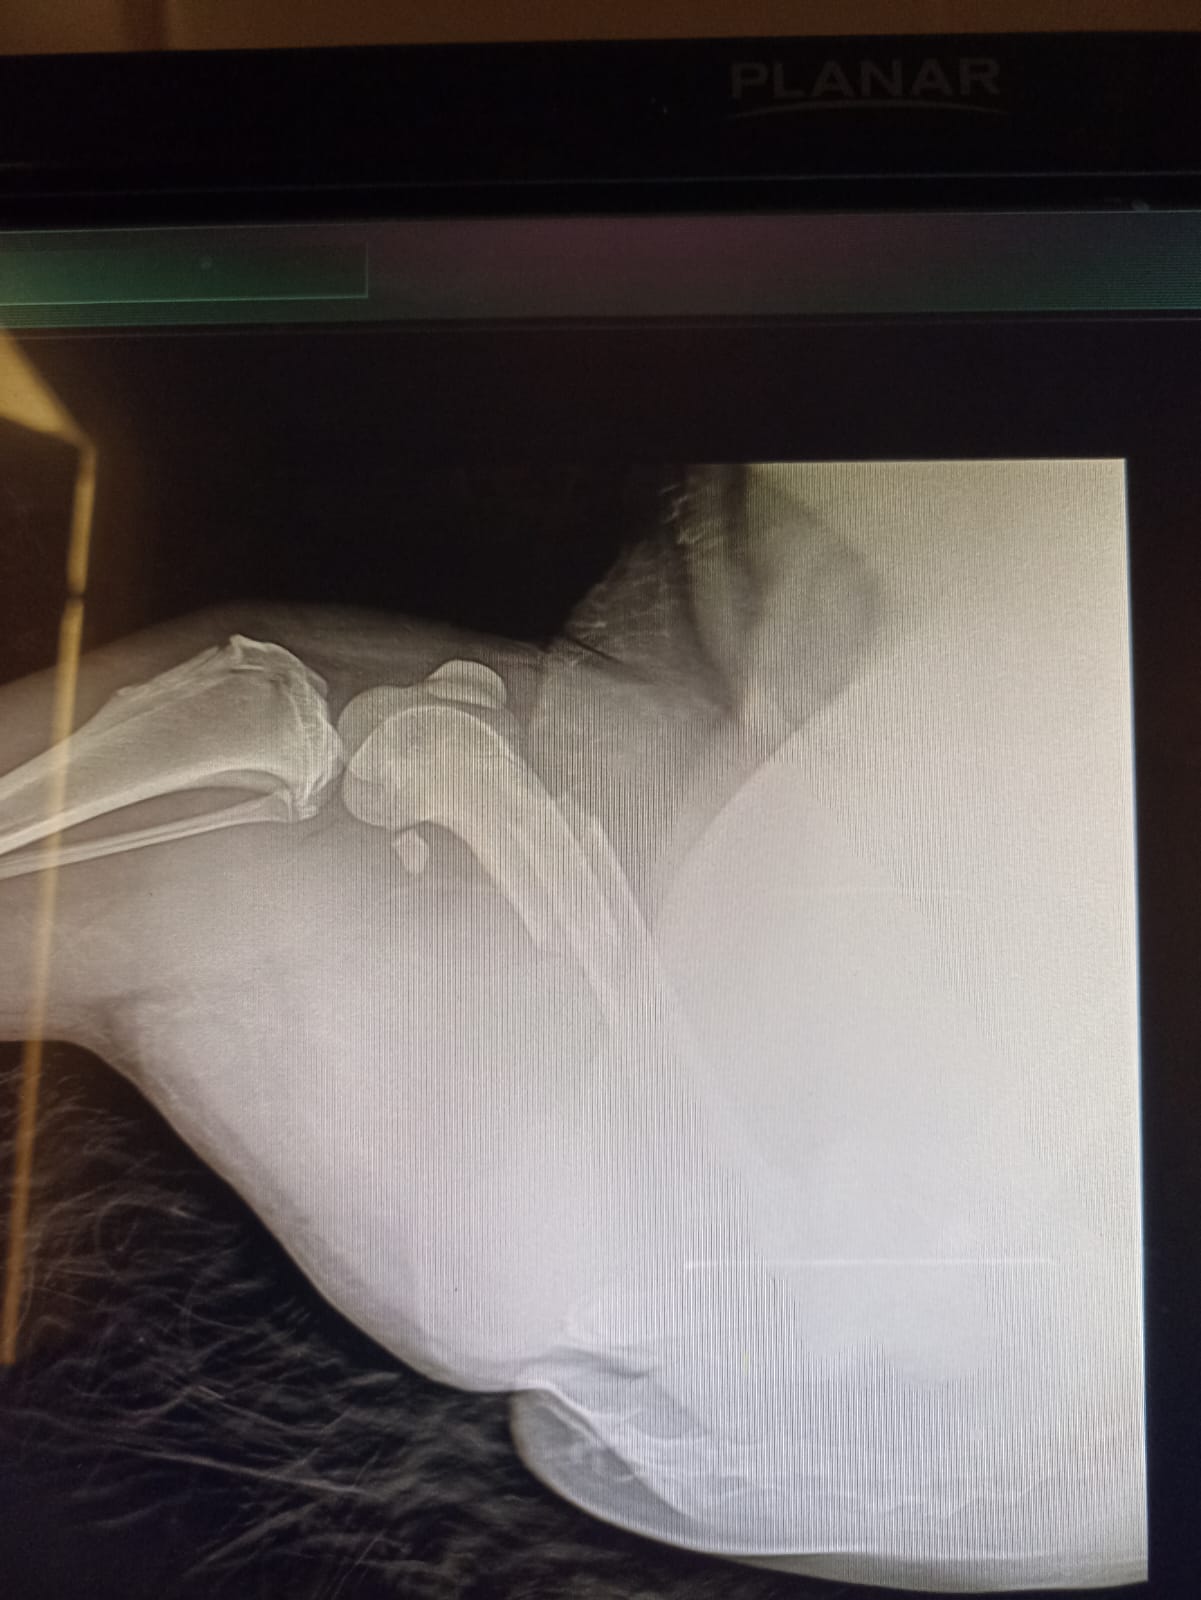

Волонтёр привела молодую суку ризена со сломанной лапой в клинику к Насте pani Stasi. Вроде перелом не сильно свежий.

Ногу будет хирург смотреть и может в ближайшее время прооперируют.

Если не дать образоваться мозоли, то все должно встать на место и будет хорошо.

Но чем больше тянуть, тем тяжелее совмещать кость....

Поэтому, чем быстрее, тем лучше. Если никаких других подводных камней нет.

Её забрала заводчица. И что-то там у них случилось, то ли лошадь понесла, то ли что, в общем, собака перепрыгивала через телегу и сломала лапу. У заводчицы тоже ключица сломана, может ещё что-то.

Операцию сделали, собрали лапу на две пластины. Выписка попозже будет.

Да, задняя правая сломана.